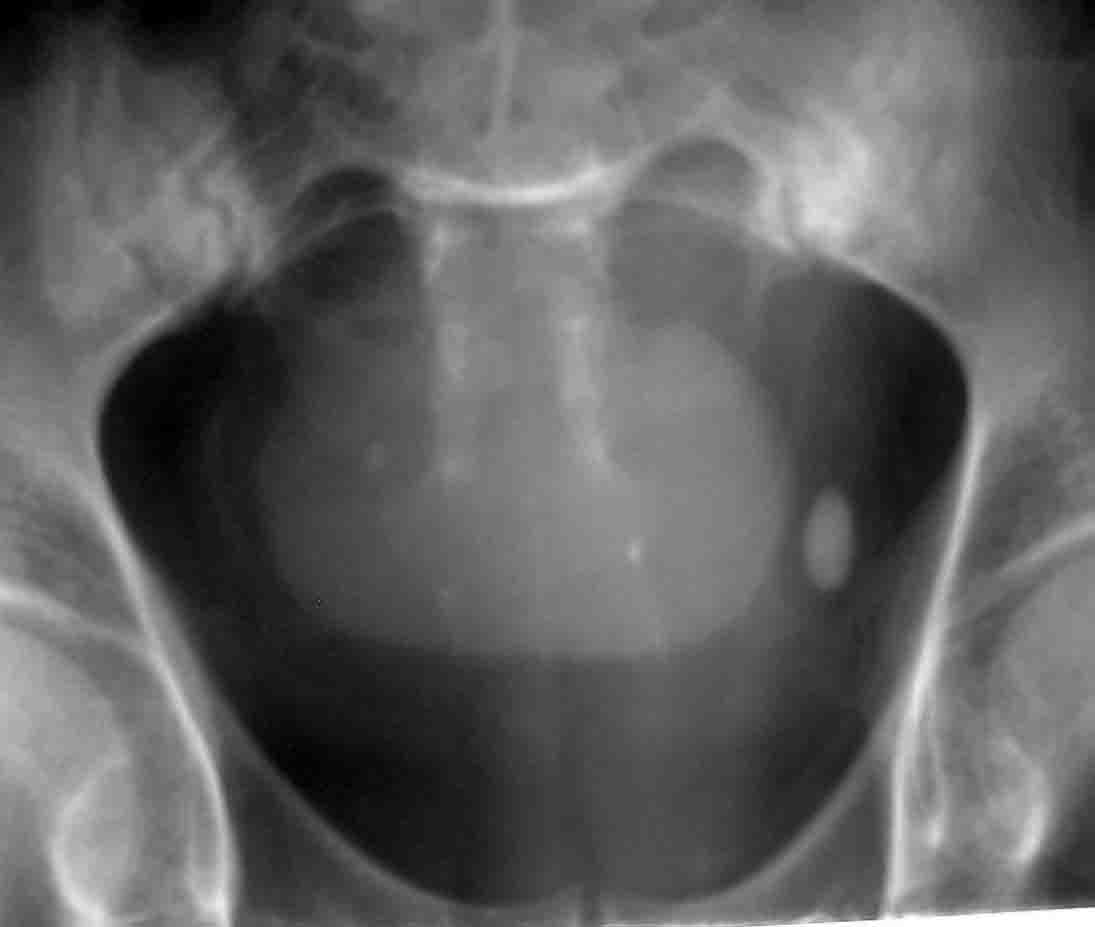

性别:男 60岁,因左侧输尿管末端结石行ivp,上述5张片分别为kub片和7分 15分 30分及120分钟延迟片.

膀胱内高密度影应为造影剂充填后改变 考虑囊肿 ,巨大膀胱隙室?, 建议b超 ct检查

1、左侧输尿管下段结石。2、膀胱炎并膀胱巨大憩室。

随着时间的延长,膀胱内高密度病灶密度逐渐增高,支持膀胱炎并膀胱巨大憩室的诊断.